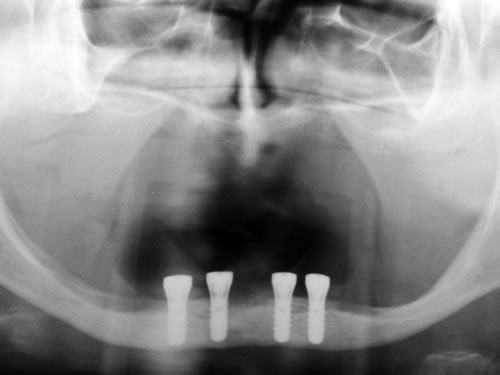

Bei der ersten Untersuchung in der Praxis hat Frau W. zunächst den Anamnesebogen ausgefüllt. Sie ist nie ernstlich krank gewesen und nimmt nur gelegentlich eine Kopfschmerztablette. In einem ausführlichen Gespräch berichtet sie ihrem Zahnarzt über die Schwierigkeiten mit den Prothesen. Nach einer ersten Untersuchung kann ihr der Zahnarzt Mut machen. Die Kieferverhältnisse sind zwar sehr ungünstig, doch so, dass eine Einpflanzung noch möglich ist. Die vorhandenen Prothesen weisen keine Mängel auf, finden aber keinen Halt. Beide Prothesen sollen nach der Einpflanzung weiter getragen werden. Nach einem Kieferabdruck wird eine Platte für den Unterkiefer angefertigt, auf der Metallkugeln befestigt sind. Sie wird wie eine Prothese eingesetzt, und es wird eine Röntgenaufnahme gemacht, die anschließend vom Zahnarzt genau vermessen wird. Es ergibt sich, dass noch eine Resthöhe von 15 mm vorhanden ist. Da auch die Breite des Kiefers ausreicht, wird ihr die Einpflanzung von vier künstlichen Zahnwurzeln empfohlen. Für ihre spezielle Kieferform ist dies die beste Lösung.

Für den Oberkiefer ist eine CT-Untersuchung notwendig, die ebenfalls mit einer Schablone durchgeführt wird. Auswertung, Planung und Implantations-Simulationen ergeben, dass sechs Implantate im vorderen Kieferabschnitt verankert werden können. Auch die Qualität des Knochens lässt eine Einpflanzung ohne weitere Maßnahmen zu. Diese Behandlung soll nach der Versorgung des Unterkiefers erfolgen.